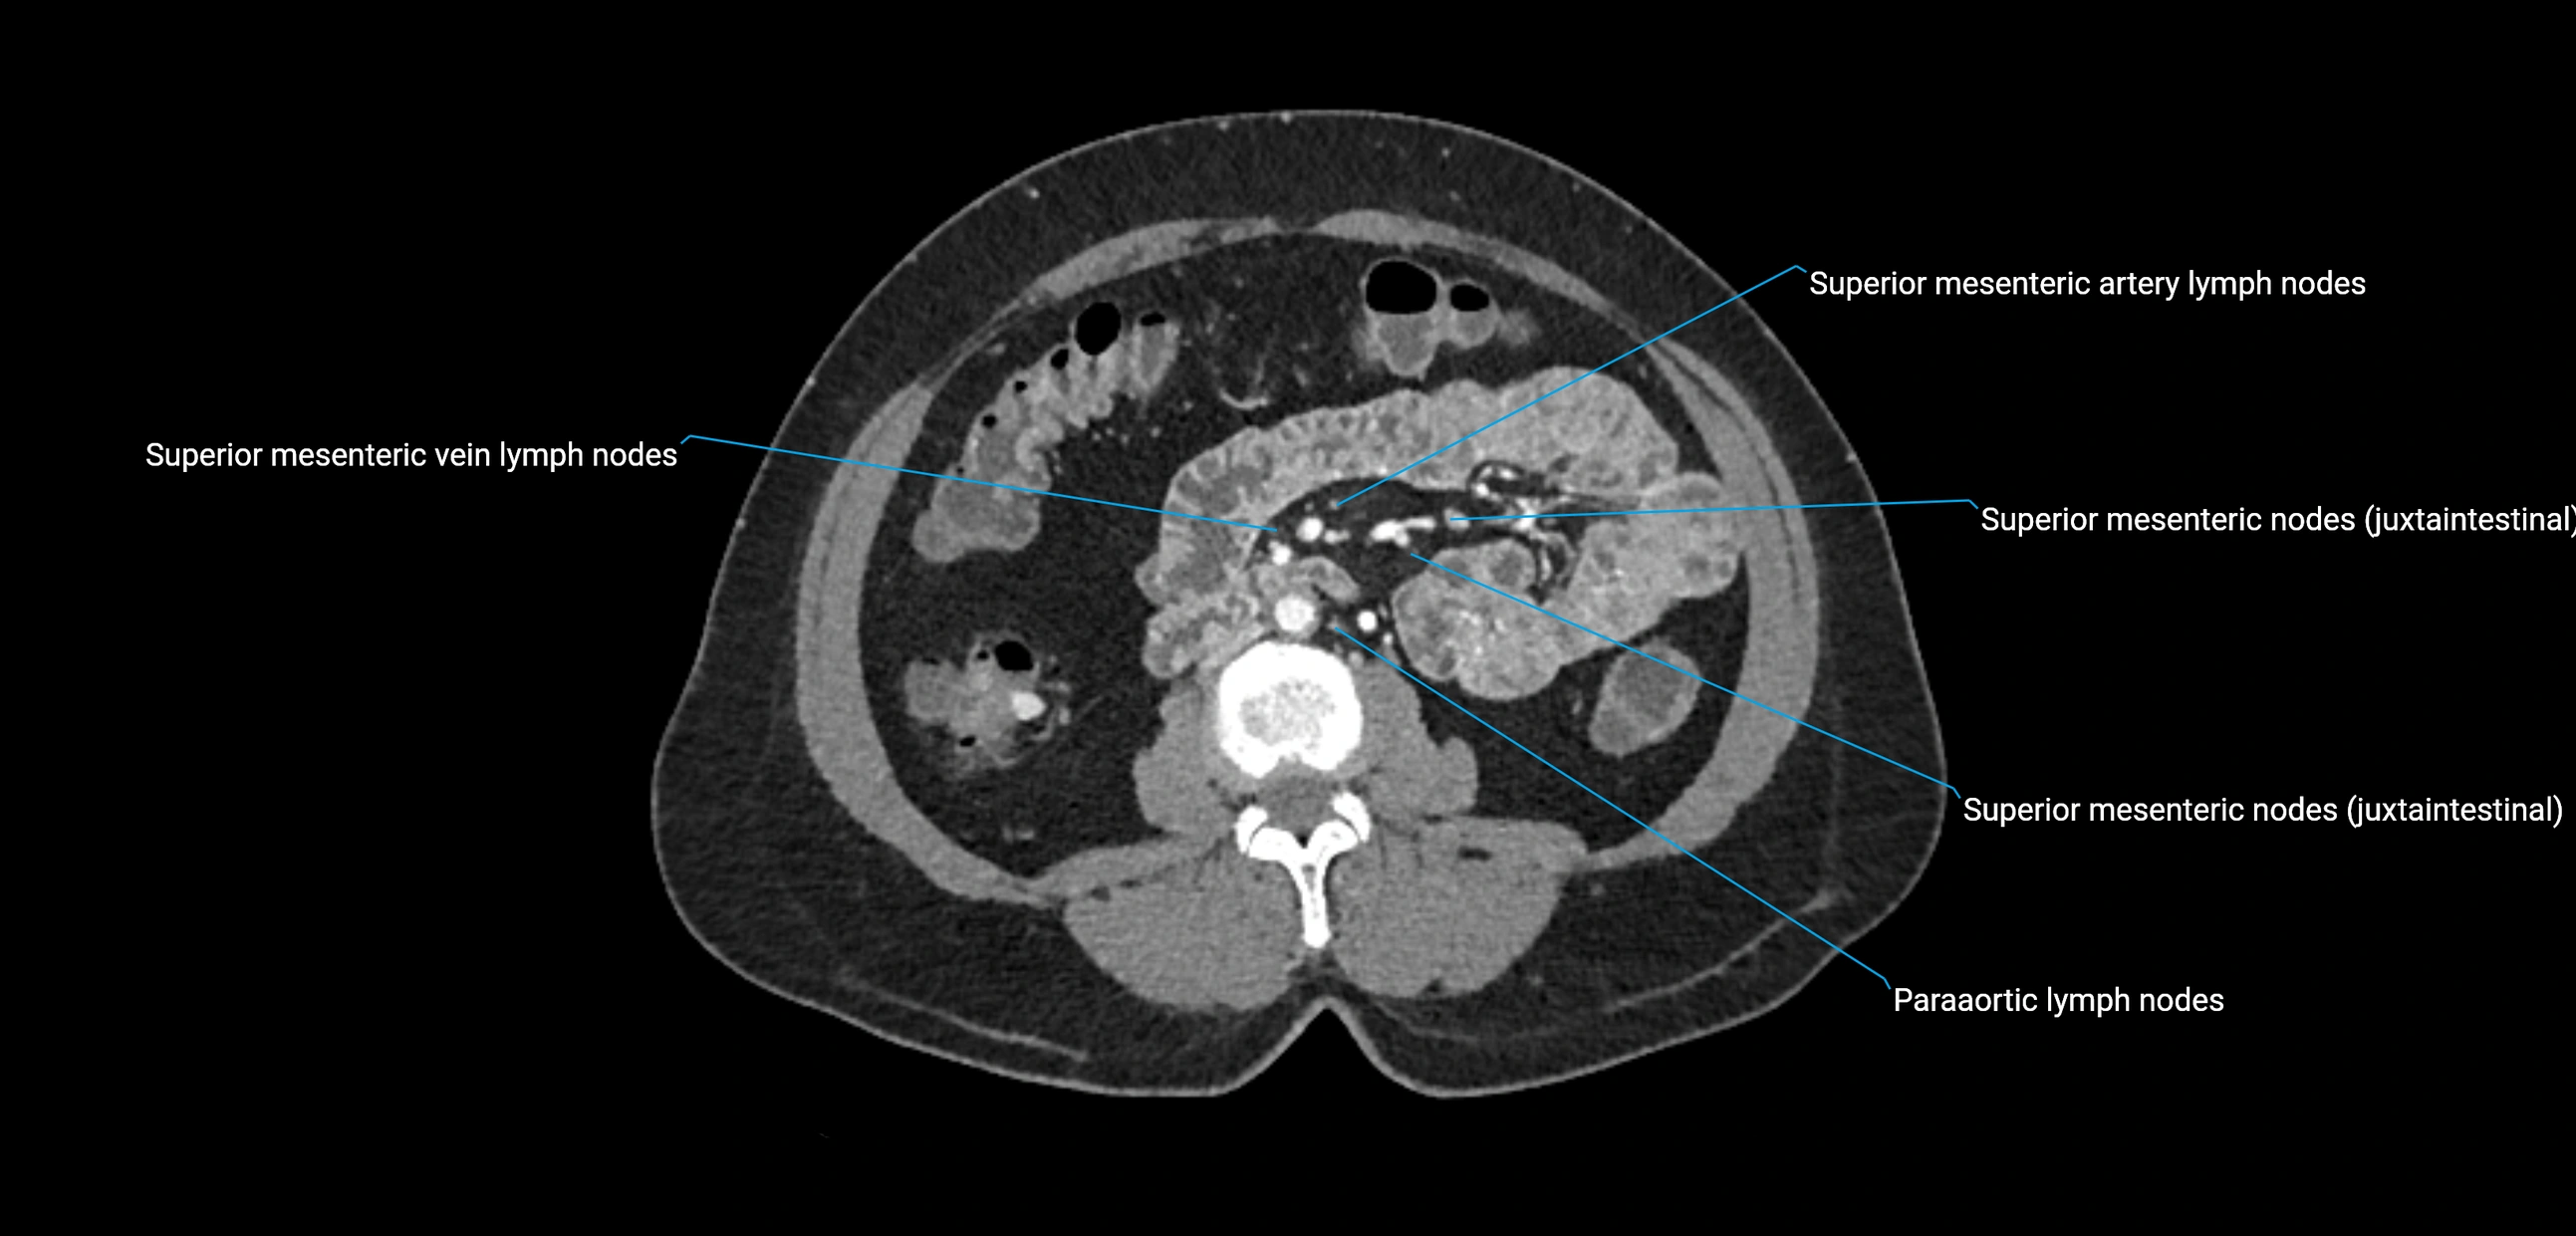

CT Appearance

CT Pre-Contrast:

• Nodes appear as soft-tissue density nodules adjacent to the aorta and IVC

CT Post-Contrast:

• Normal nodes enhance homogeneously

• Malignant nodes may show heterogeneous enhancement, central necrosis, or conglomerate formation

• Size >1 cm short axis is suspicious, though morphology and distribution are equally important